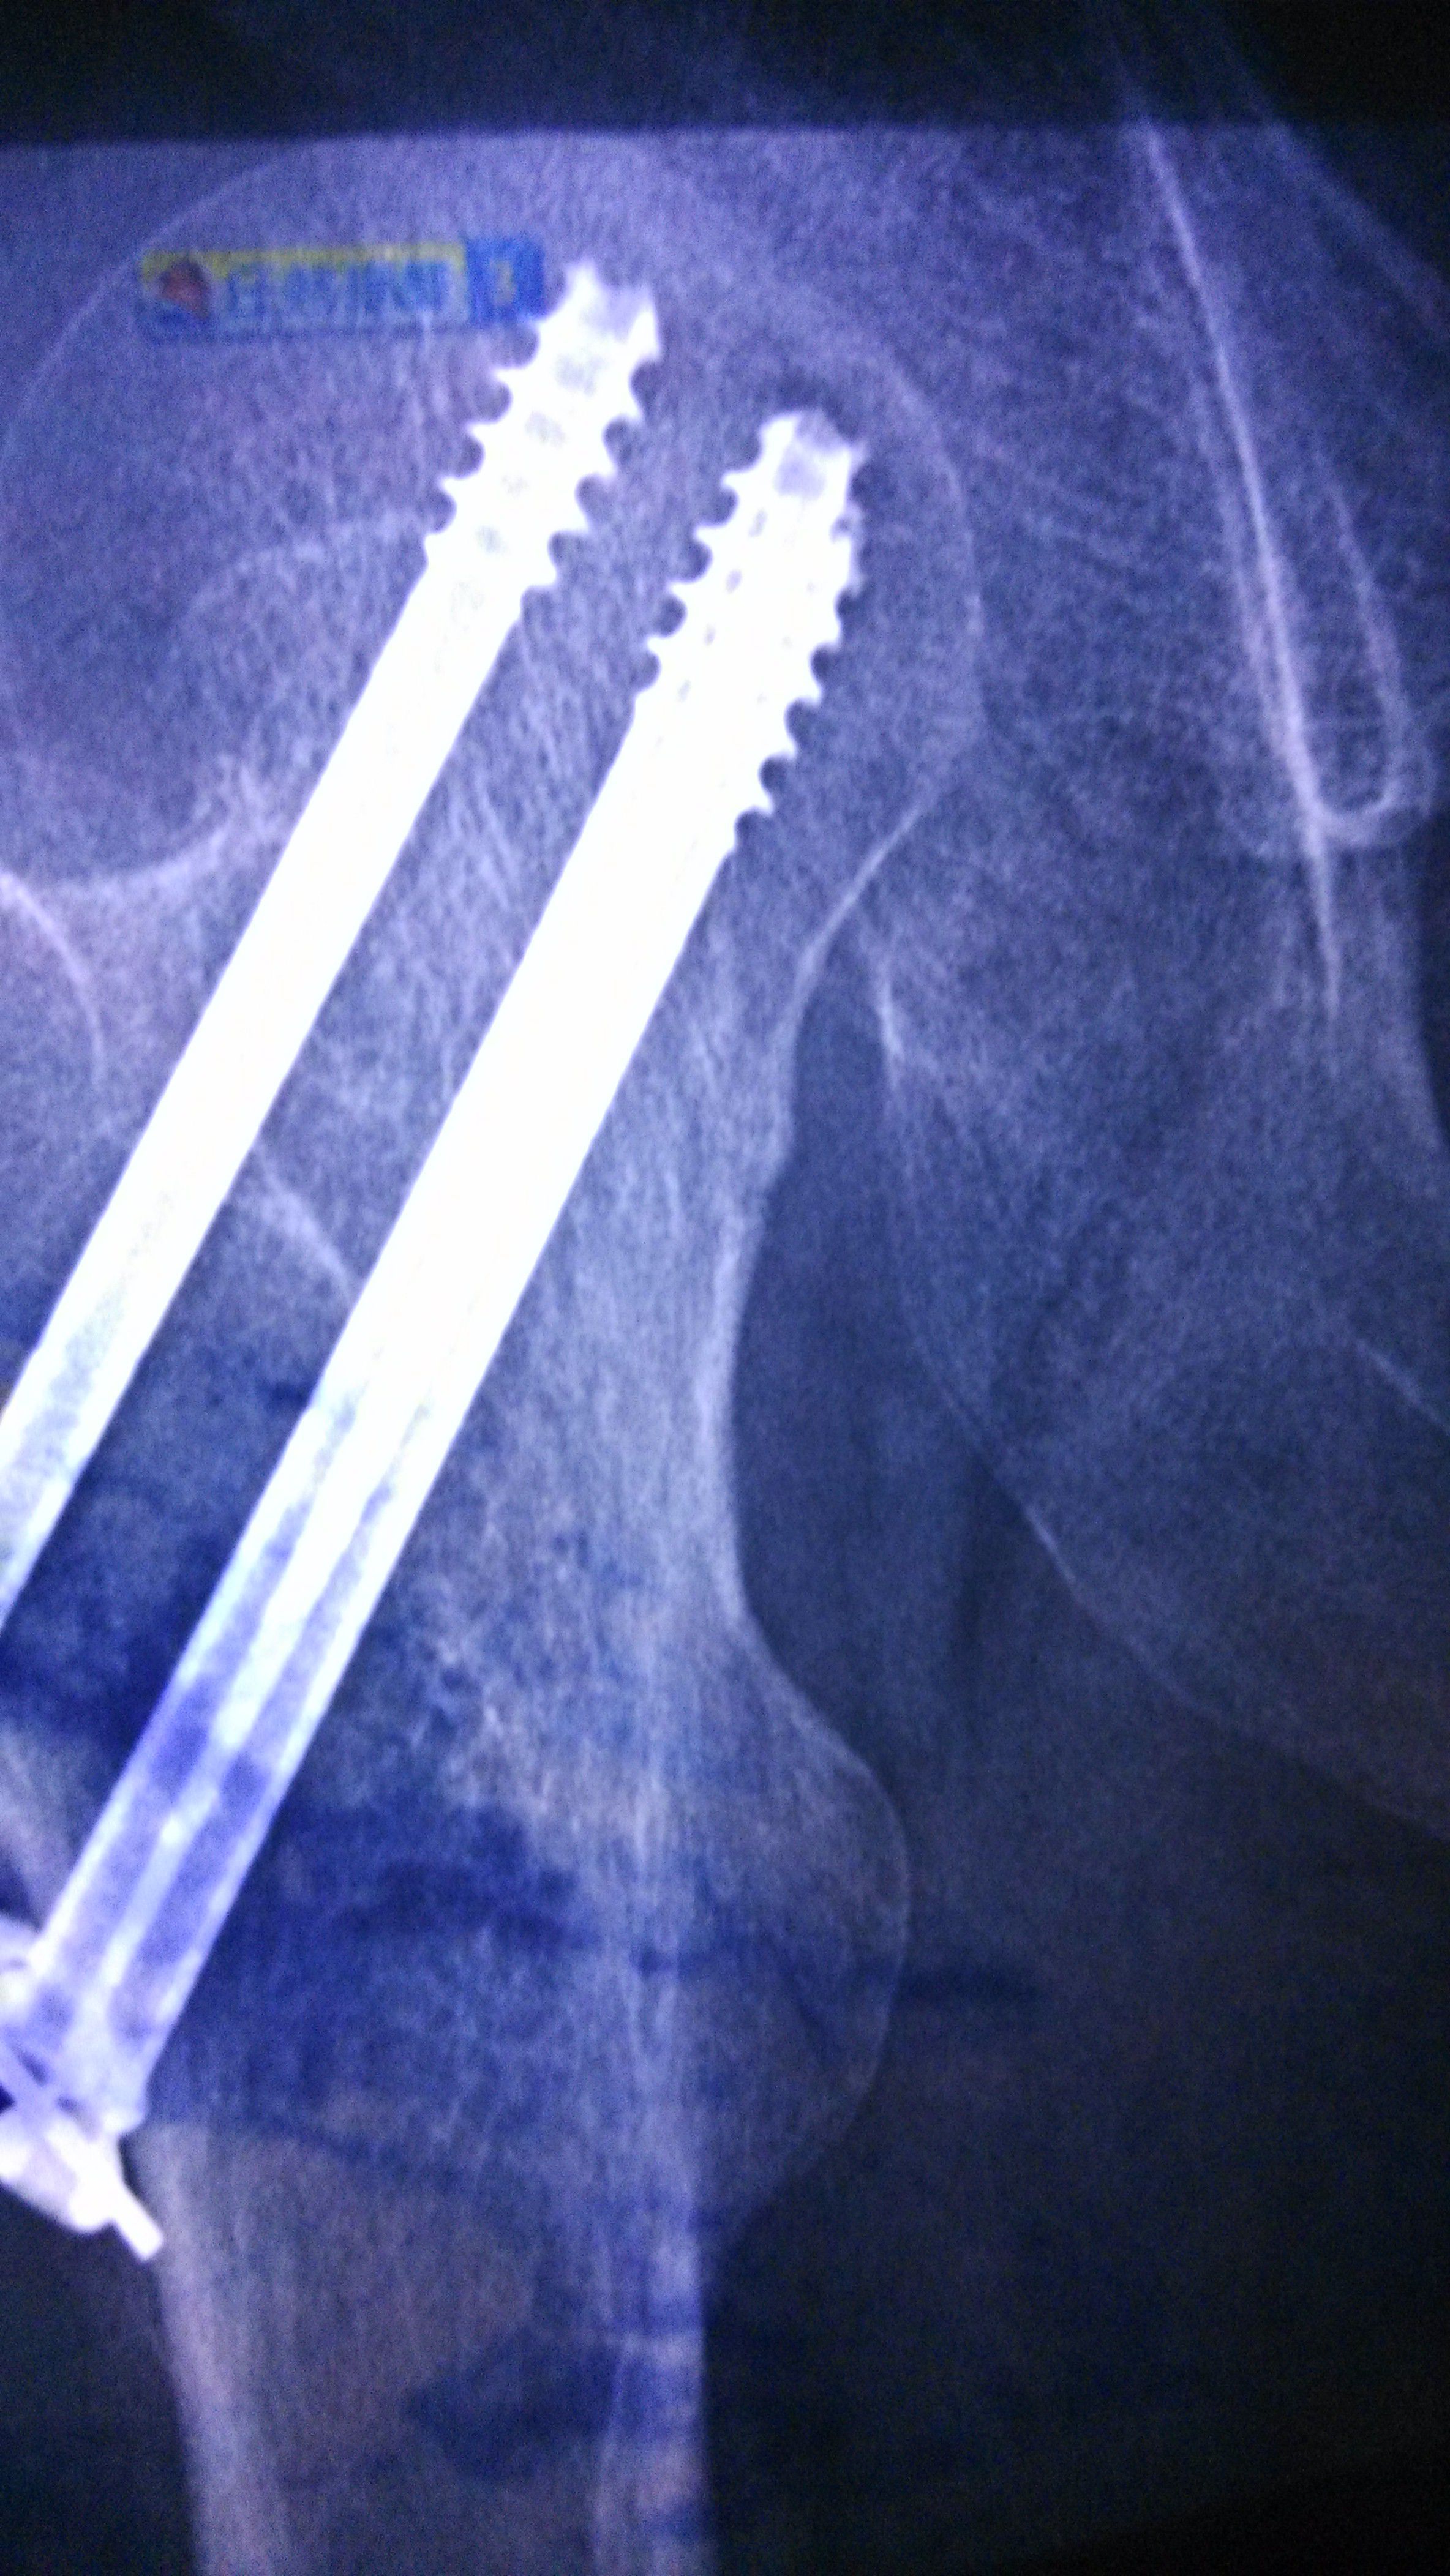

股骨颈骨折内固定七个月了,麻烦教授给看看~能不能够骑单车锻炼,谢谢了 点击展开 匿名用户 2015-06-03 21:00 满意回答 你好,股骨颈骨折内固定七个月了洞炼舞,看片队垃上,愈合不错,可糟相以锻炼的。 2015-06-03 21:08 宝宝知道提示您:回答为网友贡献,仅供参考。 相关问题 刚生完宝宝2个月这样能不能骑单车锻炼呐? 我怀孕三四周了,我每天都坚持去健身房跑步,骑单车,每次都要锻炼至少一个小时 吃饭也不忌口 股骨颈骨折七个月,现在医生诊断有坏死可能,请咨询如何进行康复治疗